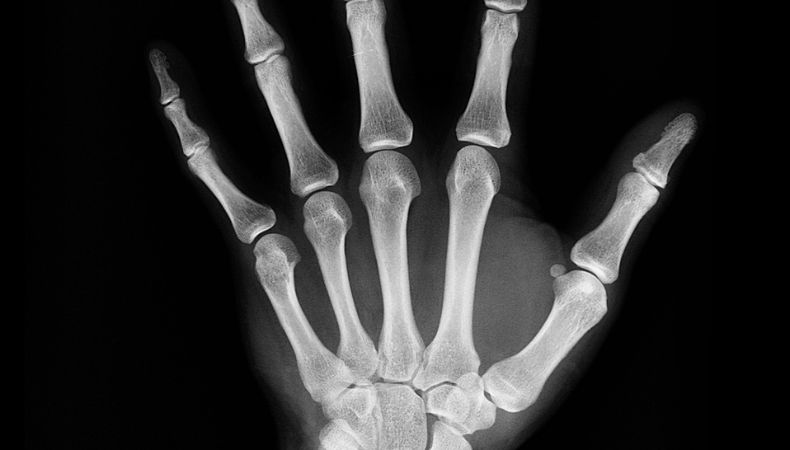

La artritis idiopática juvenil puede afectar cualquier articulación del cuerpo, pero con frecuencia perjudican en las rodillas, manos y pies de los niños.

Los especialistas acotaron que se diagnostica mediante un examen físico y una revisión de los síntomas, las radiografías y los análisis de laboratorio.